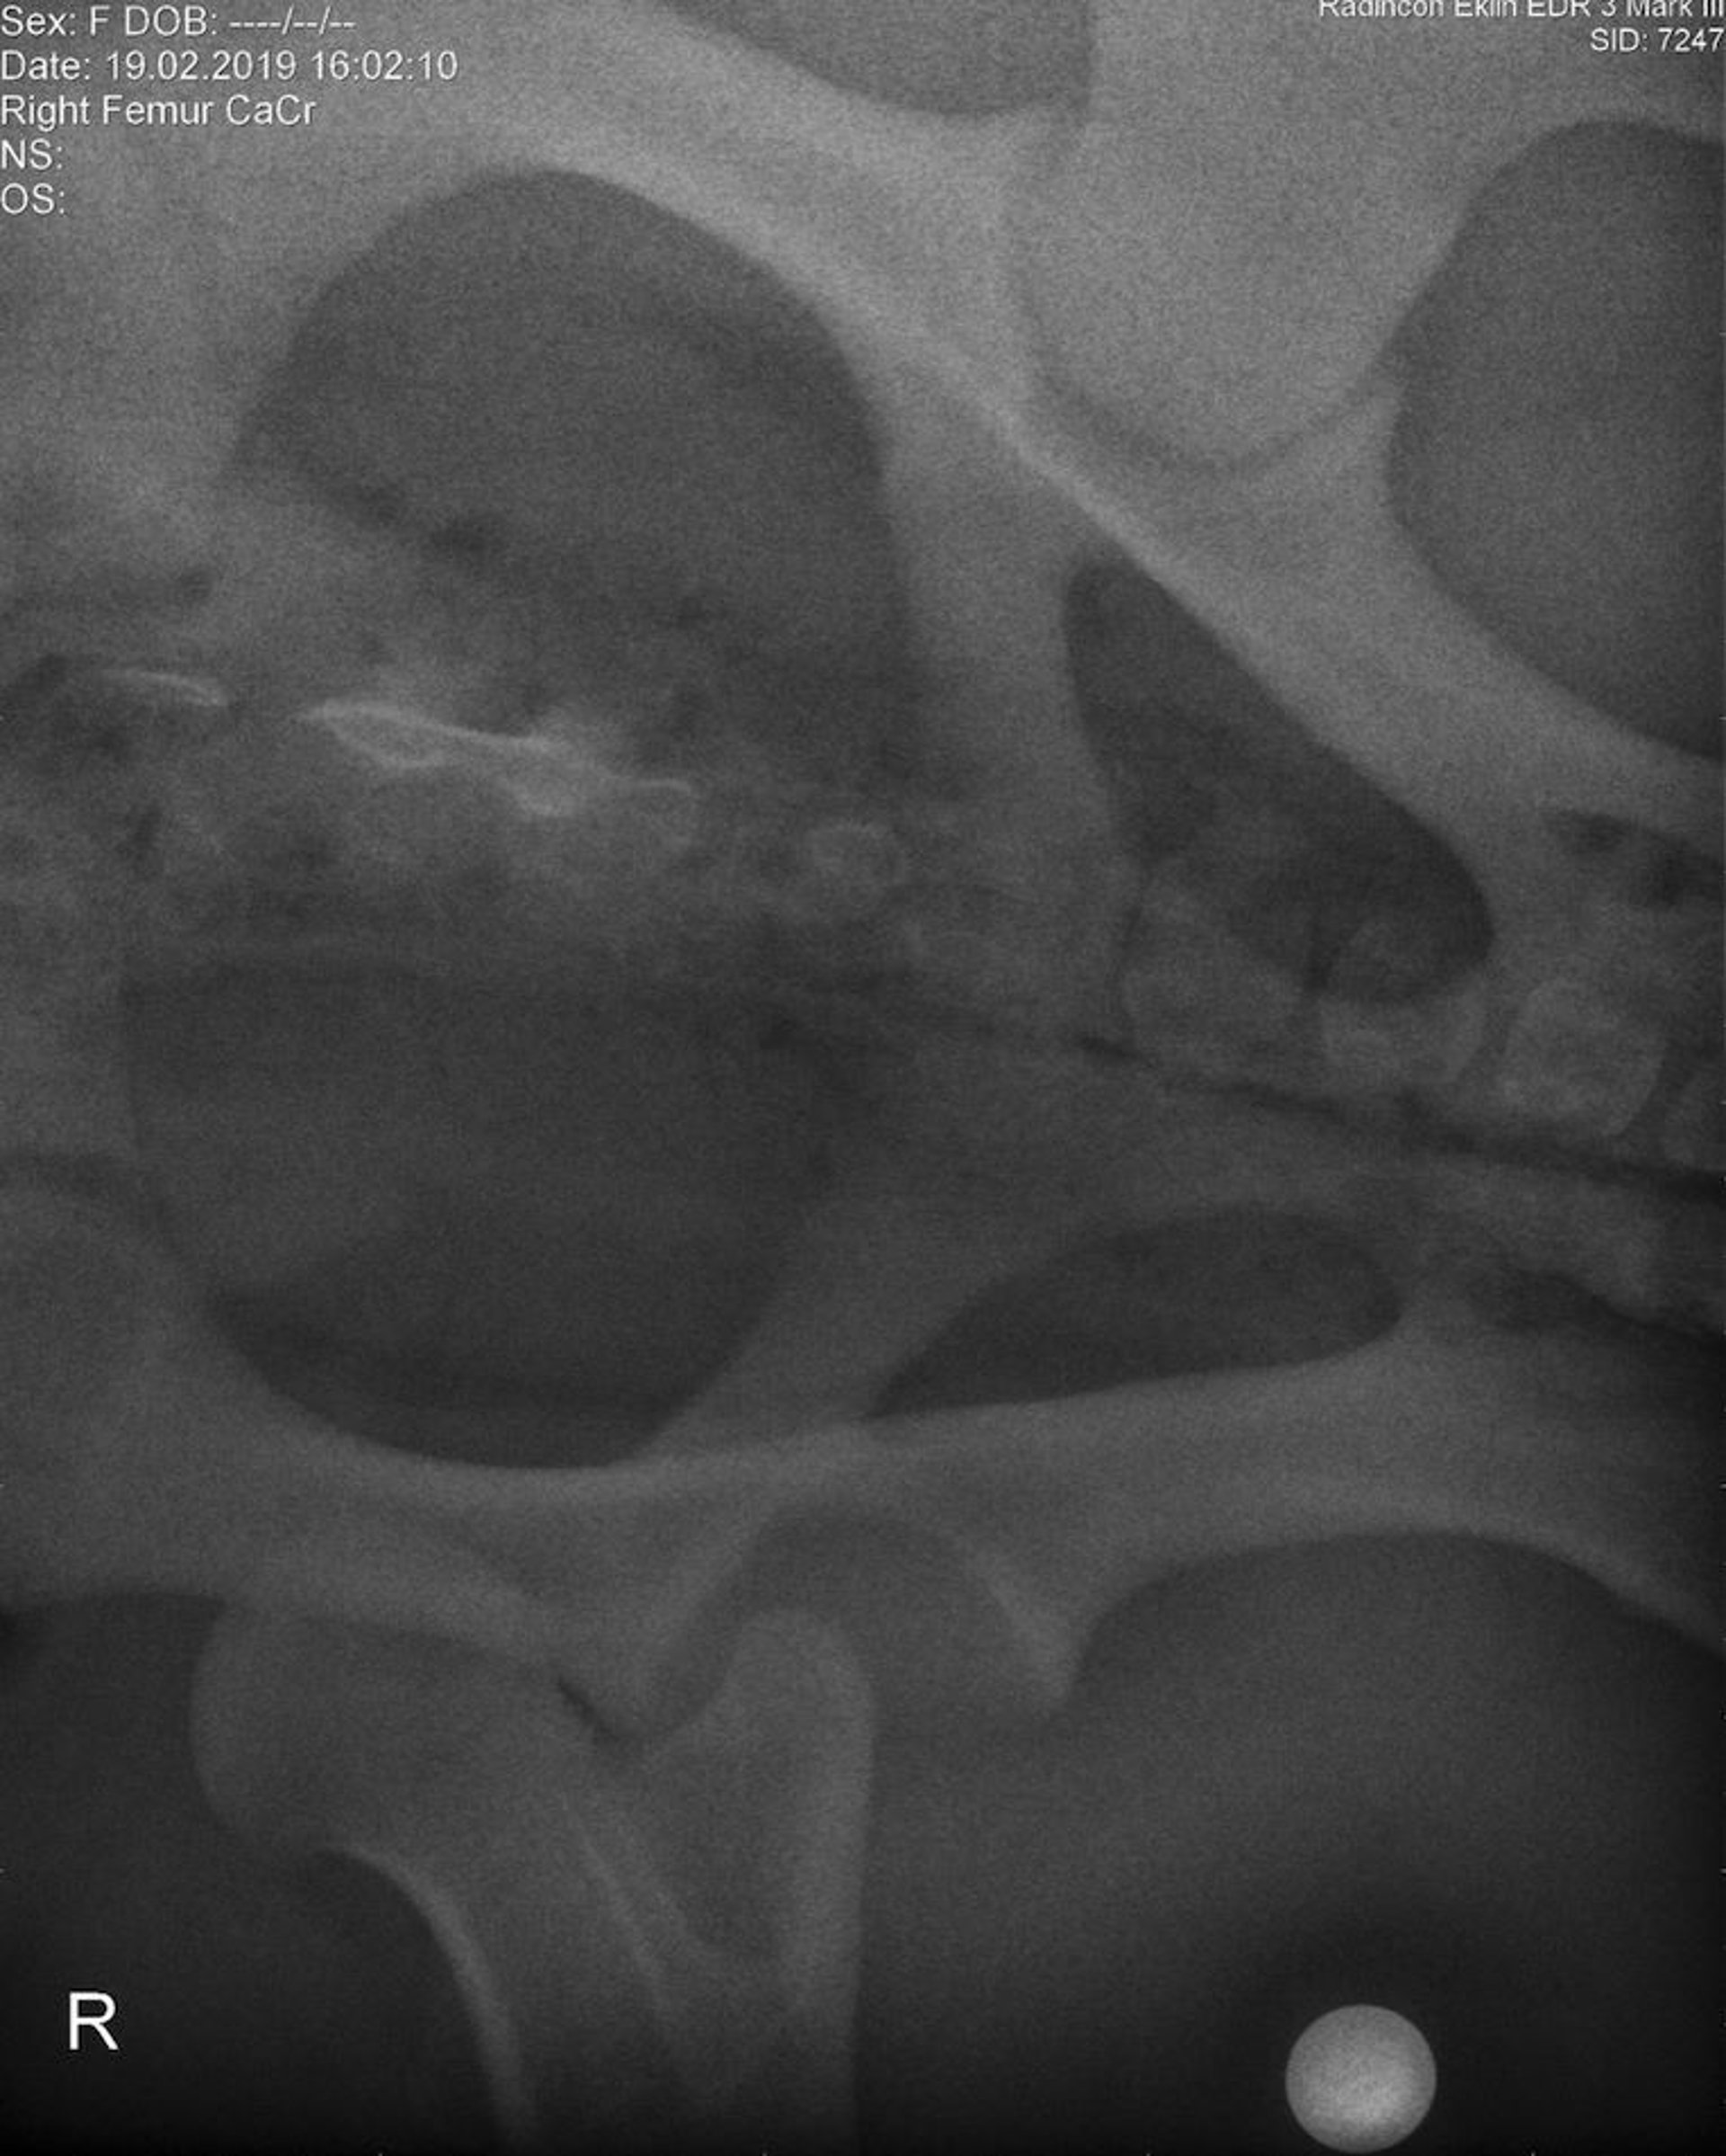

Luxación de la articulación coxofemoral, radiografía preoperatoria ventrodorsal, poni

Imagen ventrodorsal radiográfica de un poni, obtenida con el paciente bajo anestesia general antes de la cirugía, que exhibe luxación de la articulación coxofemoral derecha.

Cortesía de la Dra. Louise Cosgrove.